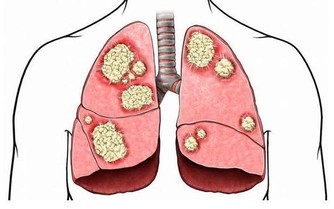

又如糖尿病、高血壓、心髒病、腎髒病、肝髒病、癱瘓、老年癡呆等疾病,都與飲食無節制有密切關係。

現代醫學已研討證實,過度的菸酒,可致使全身許多器官受損,致使180多種多見疑難病。若要從根本上解決疑問,仍是得管好嘴巴,餓餓肚子。